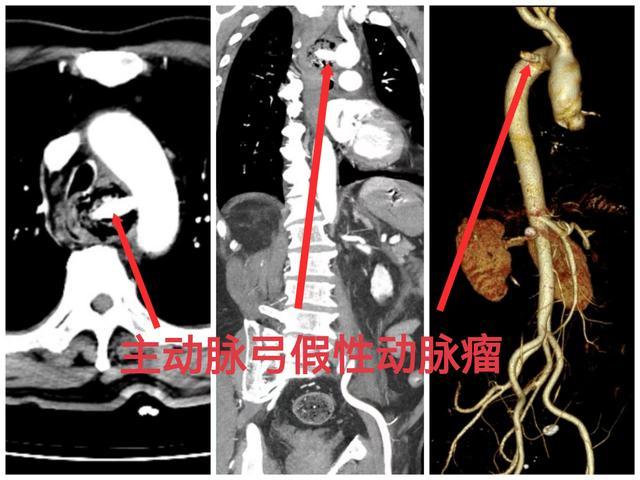

不料仅过了大约3个小时,患者再次出现呕血,怀疑有大血管损伤。紧急复查CT提示:主动脉弓内侧假性动脉瘤形成,胃腔内高密度灶。考虑假性动脉瘤破裂出血,动脉血经食管破口呕出及流入胃肠道,患者随时面临假性动脉瘤完全破裂大出血、迅速死亡的风险。

抢救室立即启动多学科会诊,介入血管外科、消化内科、普外科、急诊三部ICU人员紧急讨论、分析病情后一致认为:患者主动脉弓假性动脉瘤形成并破入食管,随时可能因大出血导致死亡,且纵膈内感染严重,可能因脓毒症进展为脓毒性休克而危及生命,应立即收入急诊ICU;